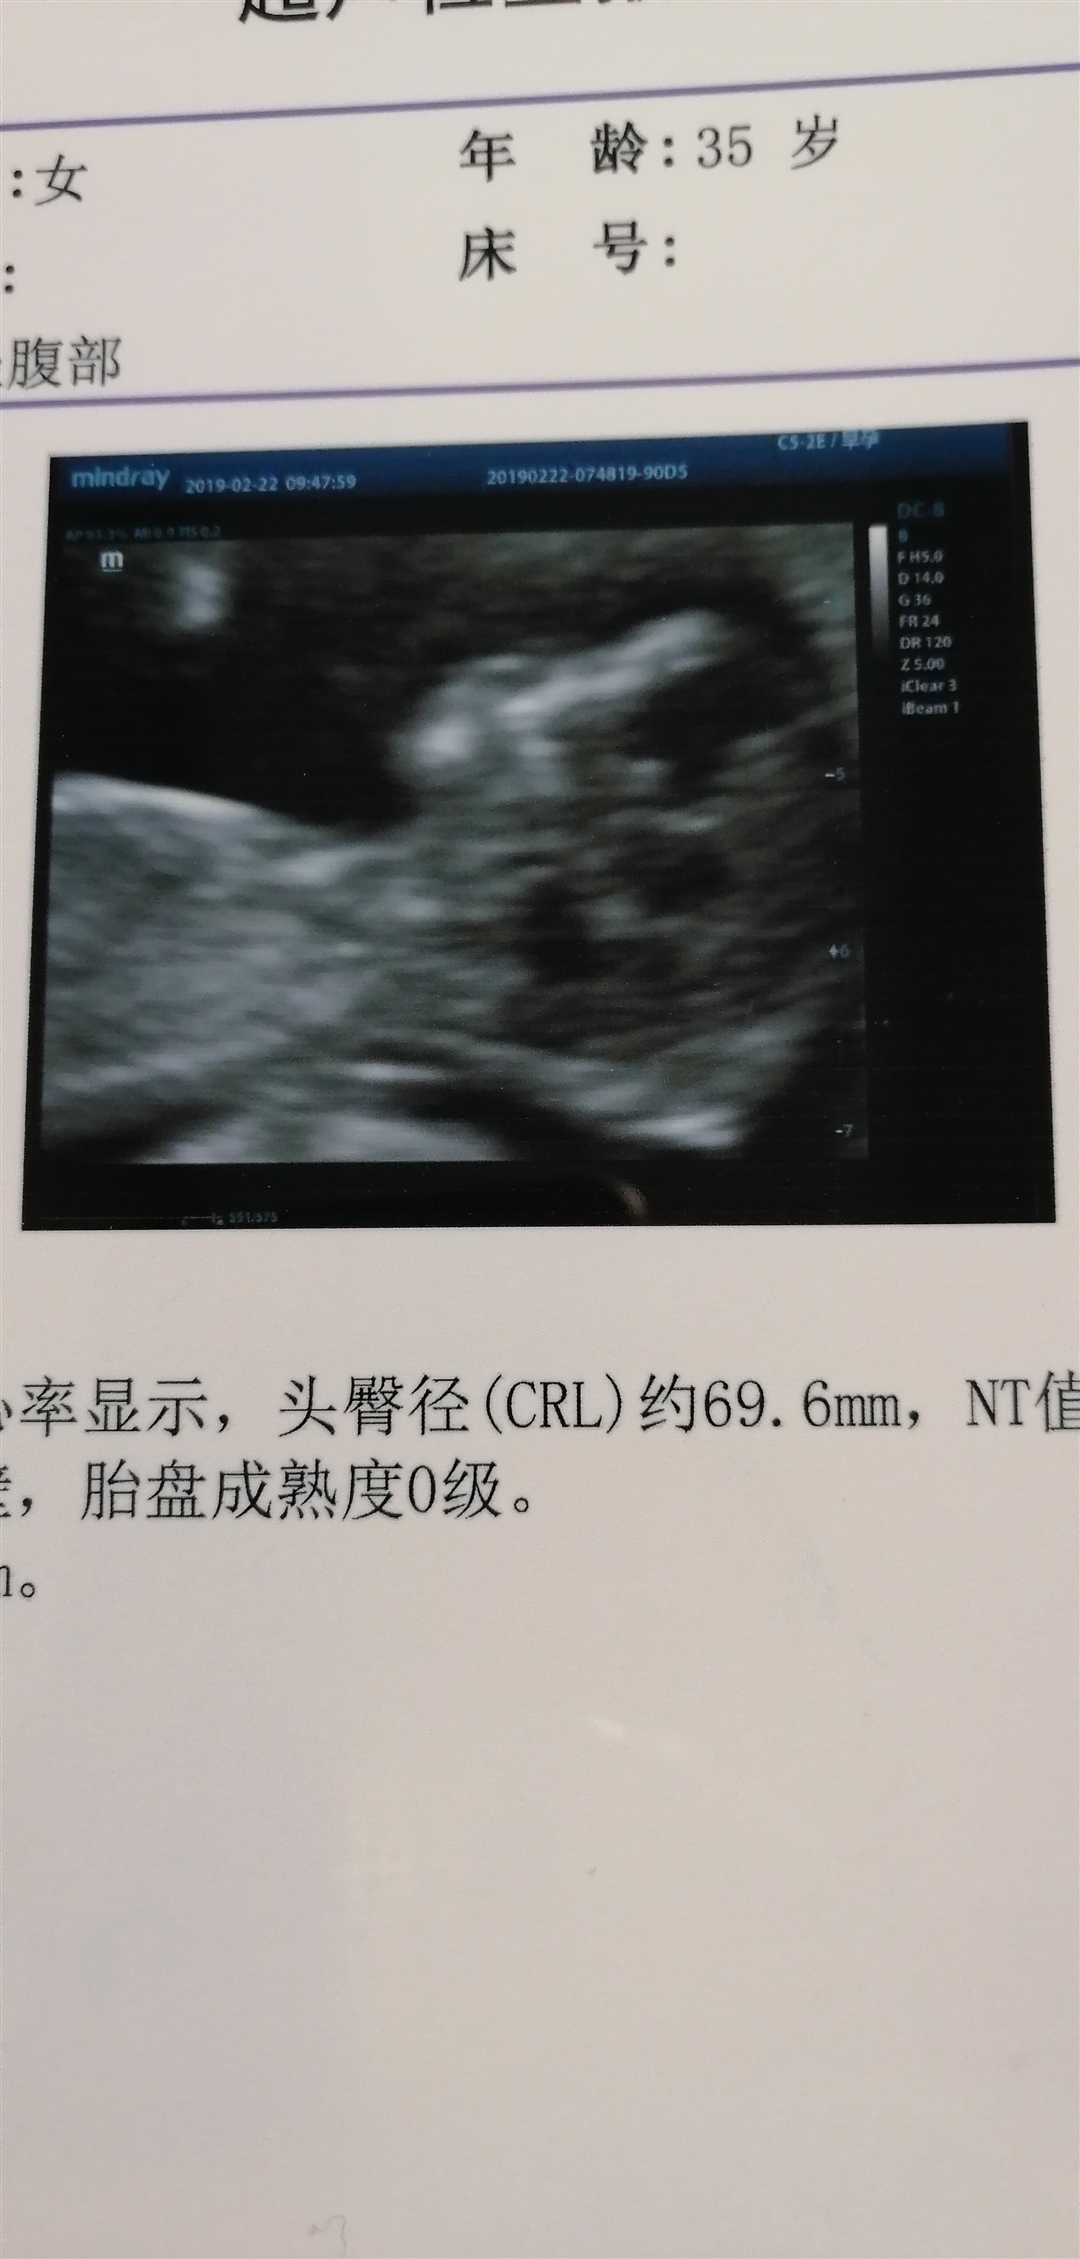

🌸june💖💯[帖主]:12 5做nt

接Nt顺利通过

都正常所有指标都很好。